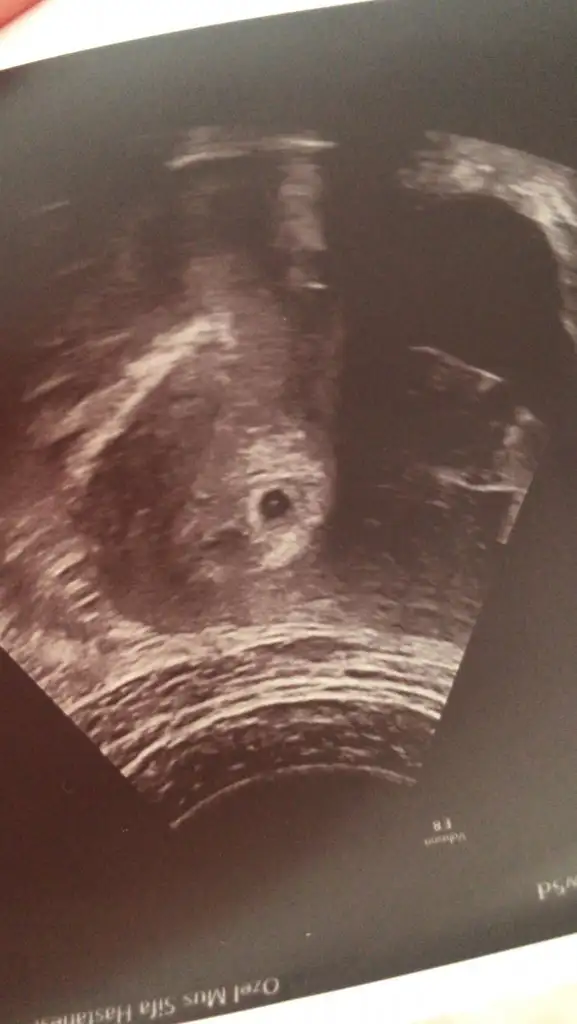

Canım ben anlamıyorum yoksa yardımcı olurdum. Benimkini atim belli kıyaslanır. Gözün aydın inşallah kalbi de atar kucağına da alırsınKızlar biz bu gün hastaneye gittik ve kesemizi gördük çok şükür.4-5 gün geriden geliyormuş ama kese var ve 4-5 gün geriden gelmesi dışında bir problem görünmedi. Dış gebelik veya kimyasal gebelik değilmiş onu da öğrendik. Ama doktorum hala %90 düşük olacak dedi ısrarla bizi en kötüsüne hazırlamaya çalıştı. Kalp atışını duymadan kesin bir şey söyleyemem dedi haftaya kalp atışı için gideceğiz. Bu günkü kesenin göründüğü Ultrason görüntüsünü paylaşacağım. Doktora soramadım yolk kesesi ve embriyo görünüyor mu diye. Anlayan arkadaşlar varsa kendi doktorlarının söylediklerinden yorum yapabilir mi

Bebek henüz görünmüyor içinde ama kese var neden düşük olacak diyor ki kanama alanı mi var?Gözünuz aydın ben olsam başka bi doktora daha giderim motivasyon önemli.Kızlar biz bu gün hastaneye gittik ve kesemizi gördük çok şükür.4-5 gün geriden geliyormuş ama kese var ve 4-5 gün geriden gelmesi dışında bir problem görünmedi. Dış gebelik veya kimyasal gebelik değilmiş onu da öğrendik. Ama doktorum hala %90 düşük olacak dedi ısrarla bizi en kötüsüne hazırlamaya çalıştı. Kalp atışını duymadan kesin bir şey söyleyemem dedi haftaya kalp atışı için gideceğiz. Bu günkü kesenin göründüğü Ultrason görüntüsünü paylaşacağım. Doktora soramadım yolk kesesi ve embriyo görünüyor mu diye. Anlayan arkadaşlar varsa kendi doktorlarının söylediklerinden yorum yapabilir mi

Bebek henüz görünmüyor içinde ama kese var neden düşük olacak diyor ki kanama alanı mi var?Gözünuz aydın ben olsam başka bi doktora daha giderim motivasyon önemli.